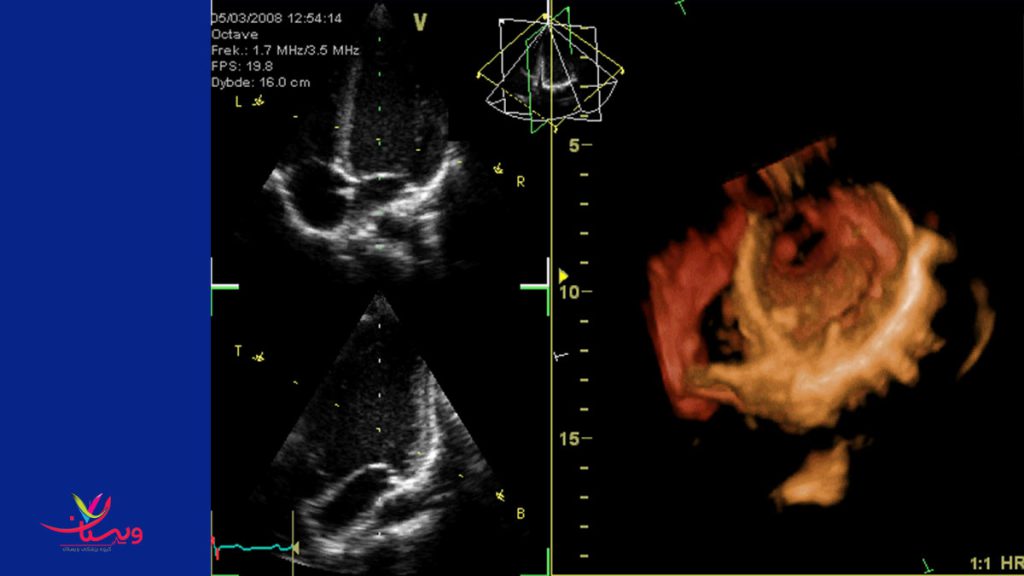

Echocardiography, also known as cardiac ultrasound, is the use of ultrasound to examine the heart. It is a type of medical imaging, using standard ultrasound or Doppler ultrasound. The visual image formed using this technique is called an echocardiogram, a cardiac echo, or simply an echo.

اکوکاردیوگرافی که به عنوان سونوگرافی قلب نیز شناخته می شود، استفاده از سونوگرافی برای بررسی قلب است. این یک نوع تصویربرداری پزشکی است که از سونوگرافی استاندارد یا سونوگرافی داپلر استفاده می کند.تصویر بصری که با استفاده از این تکنیک ایجاد می شود، اکوکاردیوگرام، اکو قلب یا به سادگی اکو نامیده می شود.

اکوکاردیوگرام چیست؟

اکوکاردیوگرام (اکو) یک طرح کلی از حرکت قلب شما است. در طول آزمایش اکو، ارائهدهنده مراقبتهای بهداشتی شما از اولتراسوند (امواج صوتی با فرکانس بالا) از یک عصای دستی که روی قفسه سینه شما قرار میگیرد برای عکس گرفتن از دریچههای قلب و حفرههای شما استفاده میکند. این به ارائه دهنده کمک می کند تا عملکرد پمپاژ قلب شما را ارزیابی کند.

ارائه دهندگان اغلب اکو را با سونوگرافی داپلر و تکنیک های داپلر رنگی برای ارزیابی جریان خون در دریچه های قلب شما ترکیب می کنند.

اکوکاردیوگرافی از اشعه استفاده نمی کند. این باعث می شود که پژواک از آزمایش های دیگر مانند اشعه ایکس و سی تی اسکن که از مقادیر کمی تابش استفاده می کنند متفاوت باشد.